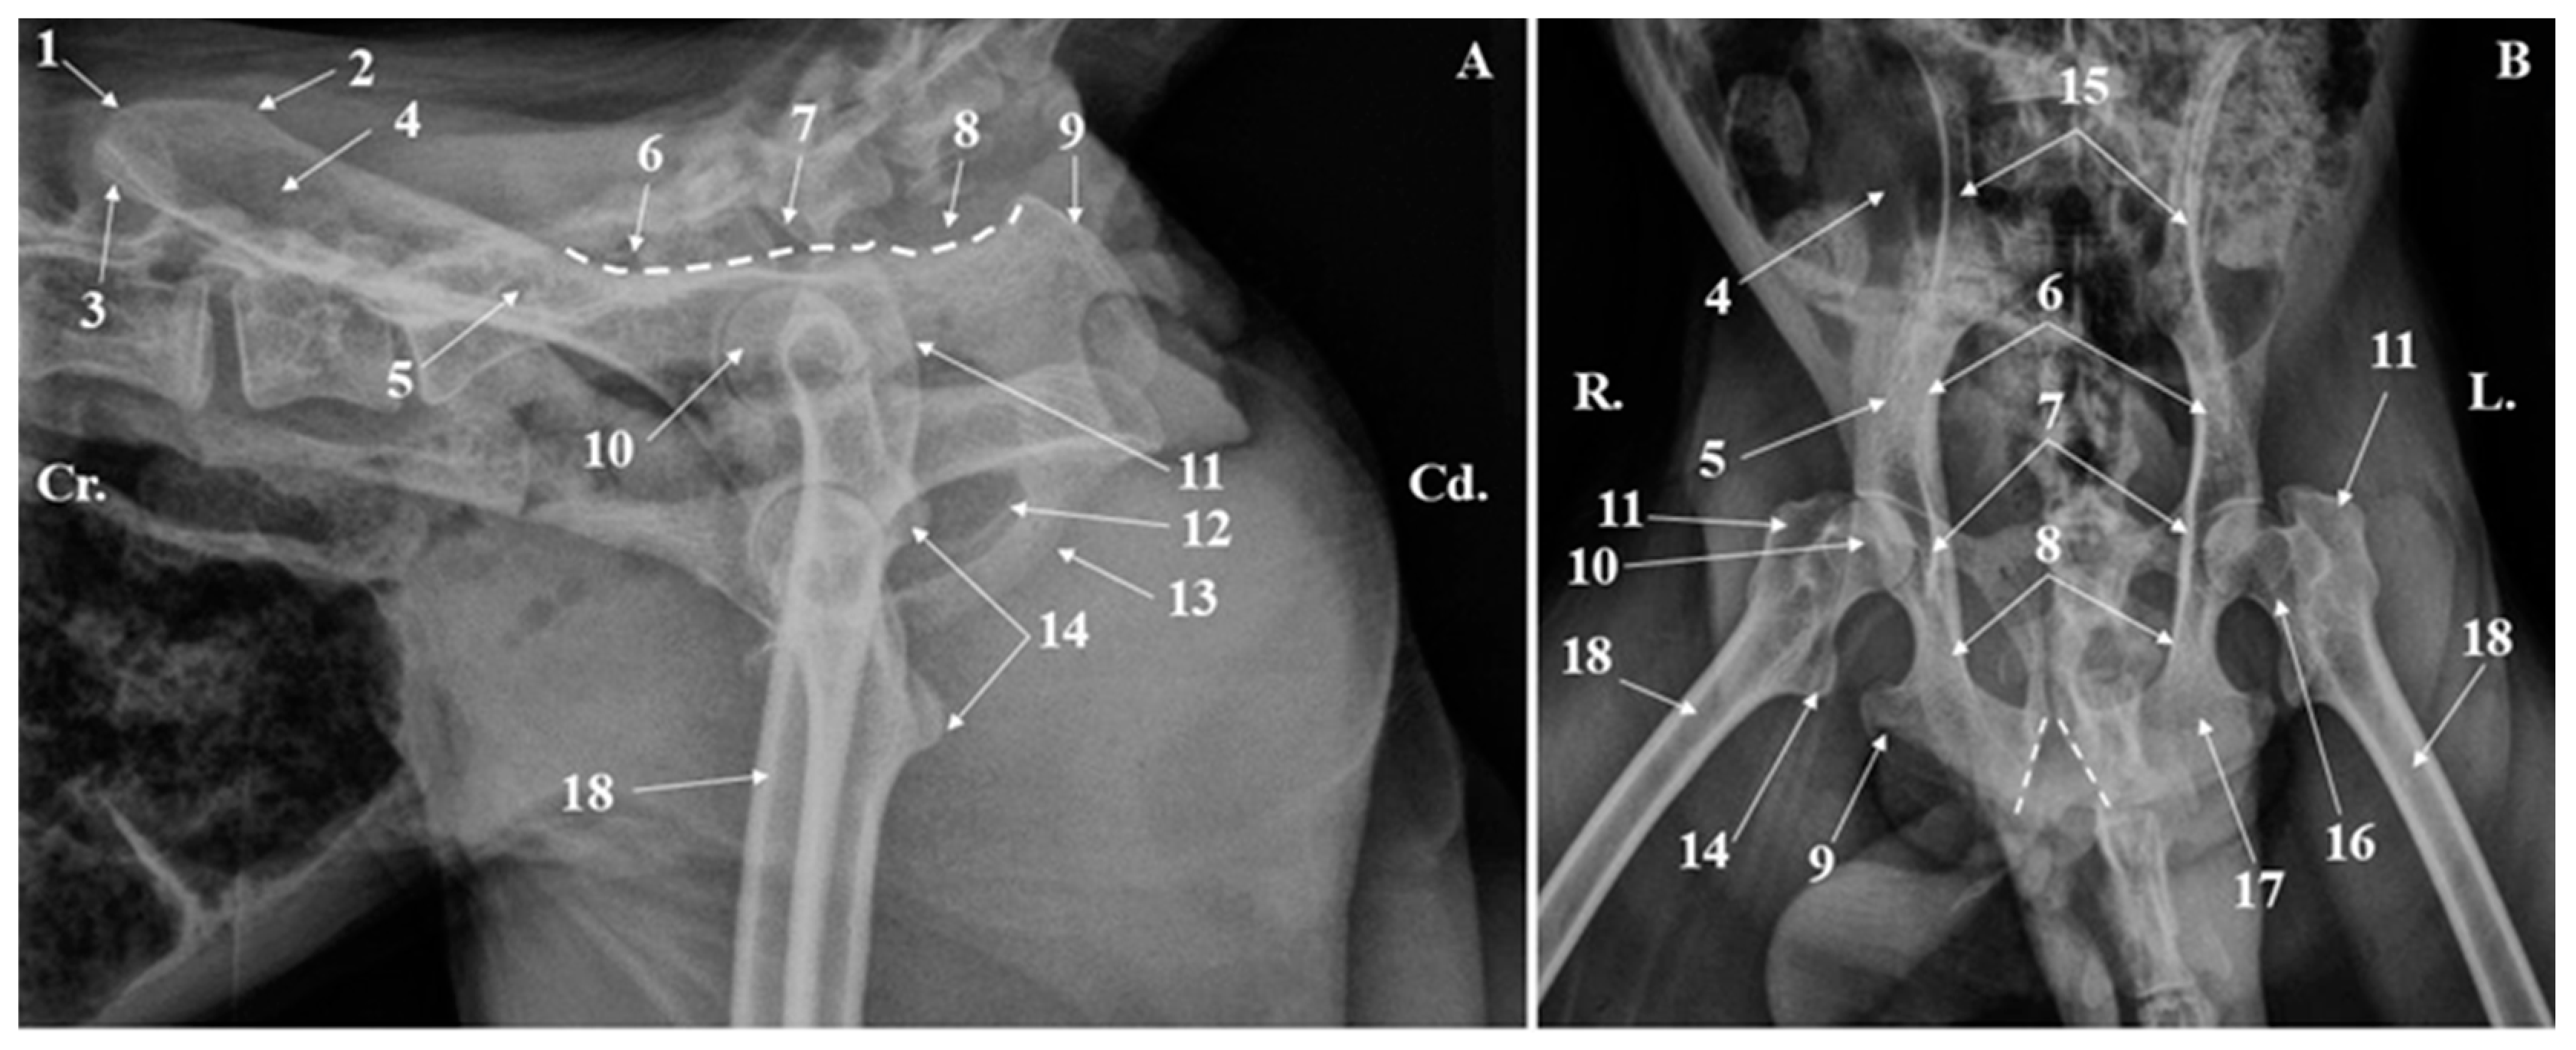

Figure 3. Coxae bones radiograph (A). Lateral–lateral projection; (B). Ventrodorsal projection. 1. Iliac crest; 2. Sacraltuberosity; 3. Coxal tuberosity; 4. Wing of the ilium; 5. Body of the ilium; 6. Greater ischiatic notch; 7. Ischiatic spine; 8. Lesser ischiatic notch; 9. Ischiatic tuberosity; 10. Femoral head; 11. Greater trochanter; 12. Obturator foramen; 13. Pelvic symphysis; 14. Lesser trochanter; 15. Ilium; 16. Femoral neck; 17. Ischium; 18. Femoral shaft. V-shape dotted lines-the ischiatic arch.

Radiographically, all the anatomical components of the coxae bones (Figure 3 and Figure 4) could be identified. Many morphological anatomical features of the ilium, ischium, and pubis bone were visible in the ventrodorsal, dorsoventral, and laterolateral projections. Even so, some anatomical structures on the skeleton were easily noticeable, while on radiographs, due to the superposition, were difficult to analyze. In this situation, the ischiatic spine, the elements of the acetabular cavity or the articular areas, located on the medial surfaces of the wings of the ilium, were hardly visible.